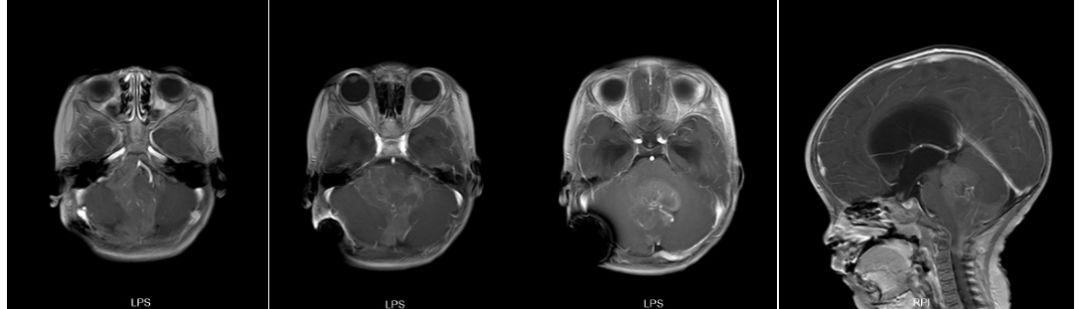

进一步评估全脊髓MR未见肿瘤转移情况。

图6. 患儿全脊髓增强MR,未见明显异常信号。